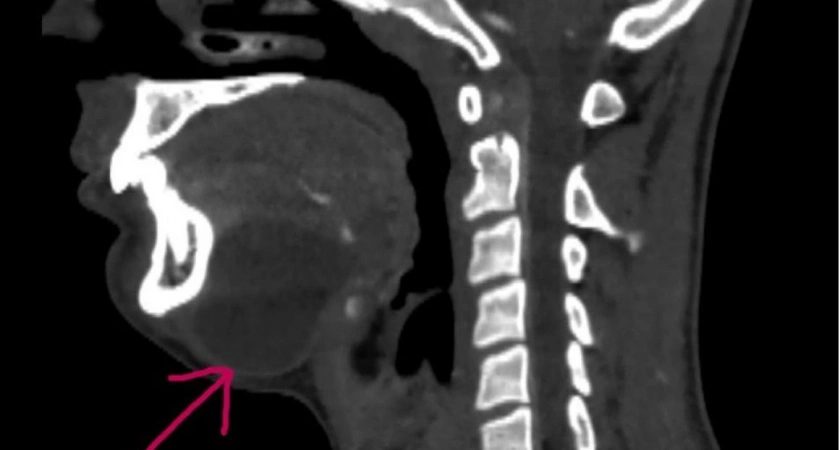

Стало известно о том, что в областной детской клинической больнице города Владимира успешно провели операцию по удалению кисты дна полости рта у подростка. Подробности рассказали в пресс-службе медицинского учреждения.

Образование, которое присутствовало у мальчика с рождения, долго не причиняло неудобств. Однако с ростом организма киста начала увеличиваться в размерах и оказывать давление на окружающие ткани, что вызвало трудности при приеме пищи и другие неприятные симптомы.

Специалисты больницы приняли решение о хирургическом вмешательстве. Во время операции киста удалили, после чего зашили рану.